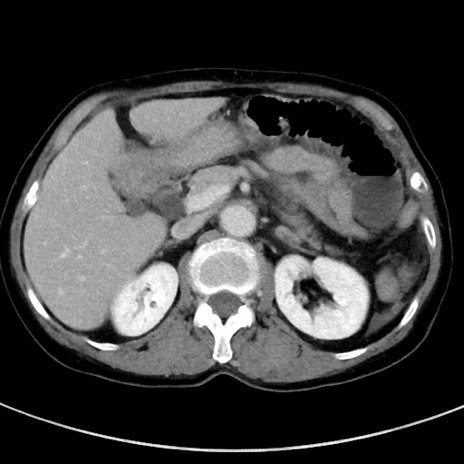

冠状断像

【症例】70歳代女性

【主訴】下腹部痛・嘔吐

【現病歴】2日前より腹痛あり。昨日嘔吐あり。症状改善しないため来院。

【既往歴】胃GISTに対して胃部分切除後。

【身体所見】BT 37.1℃、BP 128/77mmHg、腹部:平坦・軟、下腹部に圧痛あり。

【データ】WBC 10200、CRP 0.31